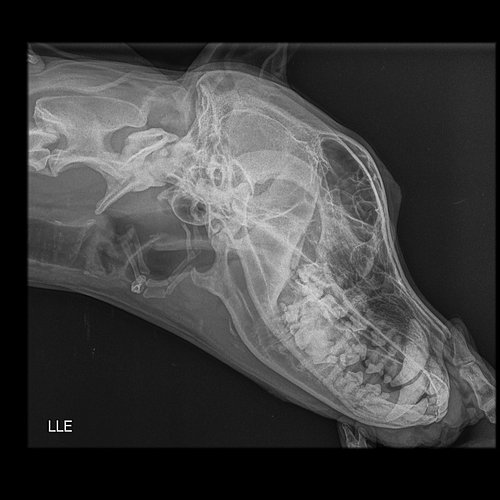

Radiografias em projeções: LATEROLATERAL ESQUERDA E DORSOVENTRAL

- Nota-se discreta proliferação óssea no aspecto ventral e medial da porção média/caudal do ramo

horizontal da mandíbula direita;

- Discreta opacificação da cavidade nasal direita;

- Cavidade nasal esquerda preservada;

- Septo nasal mantido;

- Osso nasal e frontal preservados;

- Preservação das articulações temporomandibulares;

- Em incidência dorsoventral, imagem que sugere opacificação das bulas timpânicas;

- Condutos auditivos externos sem sinais de alterações;

- Nada mais digno de nota na região em estudo, pelas incidências realizadas.